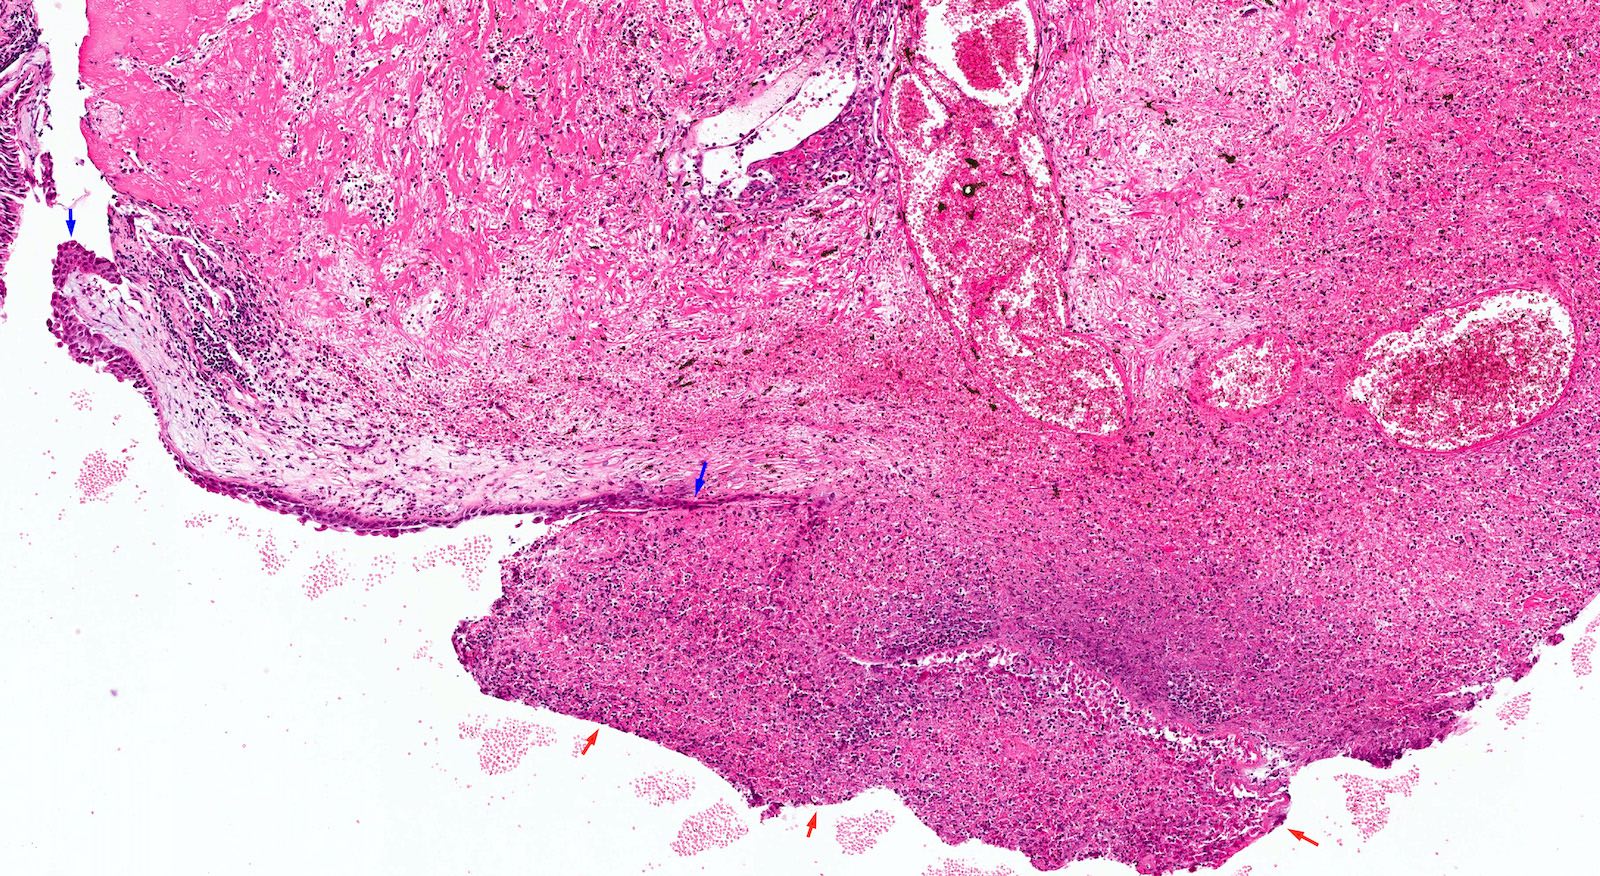

Microscopic (histologic) description

- Edematous, fibrotic or loosely myxoid stroma covered by respiratory epithelium

- Infiltrated by mixed inflammatory cells, including lymphocytes, plasma cells, eosinophils, neutrophils and mast cells

- Surface epithelium can show ulceration or squamous metaplasia

- May have bizarre stromal cells (large and pleomorphic)

- Submucosal glands are decreased or absent

- Concurrent fungal infection may be seen

- Rarely, osseous metaplasia may be present

Microscopic (histologic) images